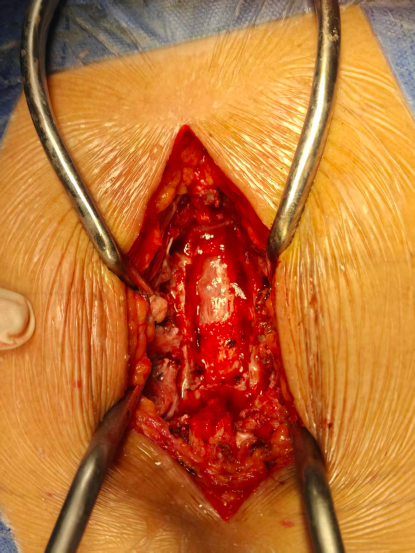

昨日完成的一例胸椎黄韧带骨化症,椎管侵占率约80%,术中采用上述的分区椎板切除技术,完整切除骨化黄韧带和部分骨化硬膜,蛛网膜保持完整。

这个病例最有趣的是神经电生理检测术前没有体感诱发电位,减压完成后20分钟,正在缝合时已经出现体感诱发电位,术后即刻患者活动略好于术前,这时候紧张的心情瞬间就轻松了。